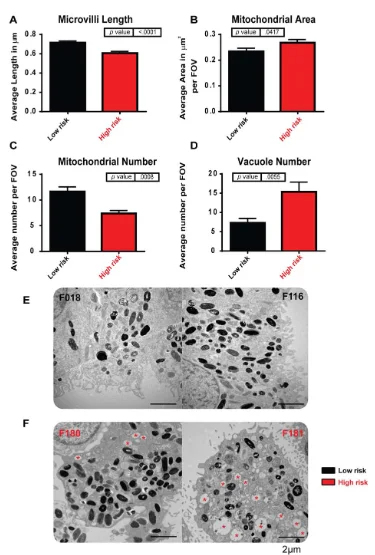

iPSC-derived retinal pigment epithelium (RPE) modeling AMD. iPSC-derived RPE generated from high-risk Y402H AMD donors (F180 and F181) show ultrastructural changes when compared to low-risk Y402H donors (F018 and F116). (A): Microvilli length is decreased in high-risk donor RPE. (B): Mitochondrial area was increased in high-risk donor RPE. (C): Mitochondrial number was decreased in high-risk donor RPE. (D): The number of vacuole structures was greatly increased in high-risk donor RPE. (E): Examples of low-risk iPSC-RPE cells: left-hand side, F018; right-hand side, F116; (F): Examples of high-risk iPSC-RPE cells: left-hand side, F180; right-hand side, F181; red asterisk indicates vacuoles. Image Credit: Newcells Biotech

The mechanisms underlying age-related macular degeneration (AMD) are poorly understood, making RPE and patient-derived retinal organoids extremely useful for disease modeling. Although the ARMS/HTRA and complement genes are known to raise the risk of AMD, it is still unclear how the other genes contribute to this increased risk.

Newcells have produced iPSC-derived RPE to model AMD from people with low- and high-risk CFH (Y402H) complement polymorphisms. In comparison to low-risk individuals, the high-risk iPSC-derived RPE cells exhibit traits typical of AMD, such as cellular, structural, and functional deficiencies linked to inflammation, cellular stress, and the buildup of lipid droplets and deposits that resemble AMD. Both the companion RPE and retinal organoids can be used for these investigations.